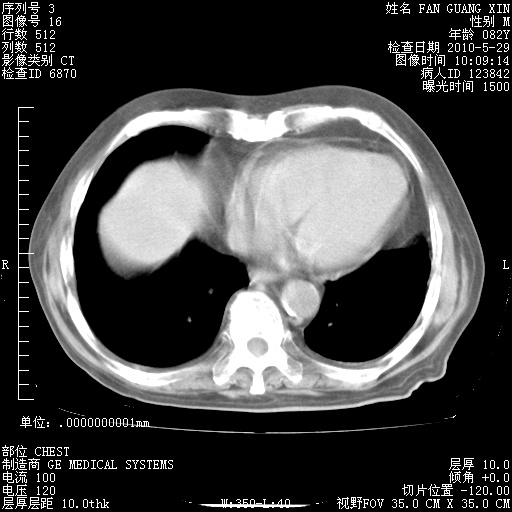

治疗3周后的肺部CT纵隔窗

再治疗10天后的肺部CT 纵膈窗